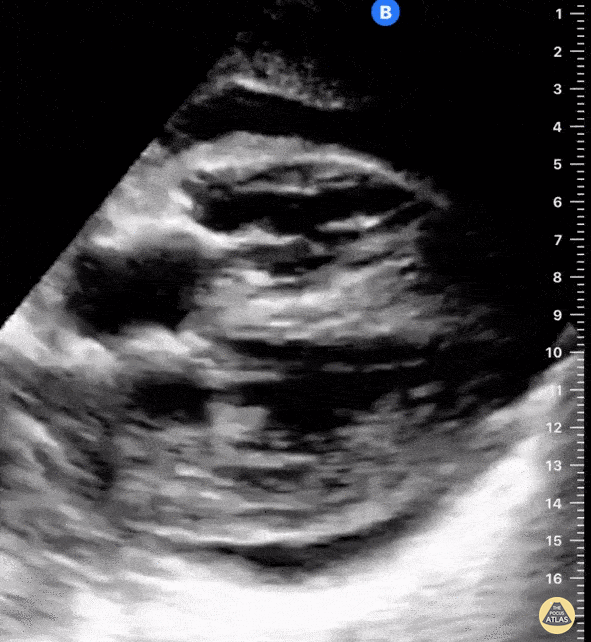

A 39-year-old female with known metastatic lung cancer complicated by multiple pulmonary emboli on apixaban presented with worsening dyspnea and productive cough over one week duration. POCUS identified a large, circumferential pericardial effusion (appreciated in multiple views; subcostal view shown here). Of note, she had echocardiographic findings consistent with tamponade physiology including early right ventricular (RV) diastolic collapse and right atrial systolic collapse. She also has evidence of RV strain demonstrated by flattening of her interventricular septum with ventricular interdependence (the latter findings are likely secondary to underlying chronic thromboembolic disease and pulmonary hypertension). Shahad Al Chalaby, MD. PGY3 Internal Medicine. Highland Hospital. Alameda Health System Residency Program. Oakland, CA, USA. @shahad_Chalaby Adam Mortimer, DO. PGY1 Internal Medicine. Highland Hospital. Alameda Health System Residency Program. Oakland, CA USA.